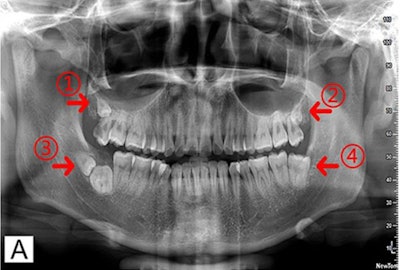

To get a better visual of the man's teeth, a dental panoramic tomogram was taken. It showed that dental caries had already approached the distopulpal horn, and there was no low-density shadow around the apical root, which led them to determine that the irreversible pulpitis caused his pain, the authors wrote. The patient also underwent CBCT with 3D reconstruction. Overall, imaging revealed the following:

- Two maxillary bilateral distomolars located at the buccal side of adjacent third molars

- One mandibular distomolar with the adjacent third molar contacted by occlusal surfaces while roots were pointed oppositely, which were diagnosed as kissing molars

- One mandibular third molar on the left with a large crown and a tapering root, which would be considered macrodontia